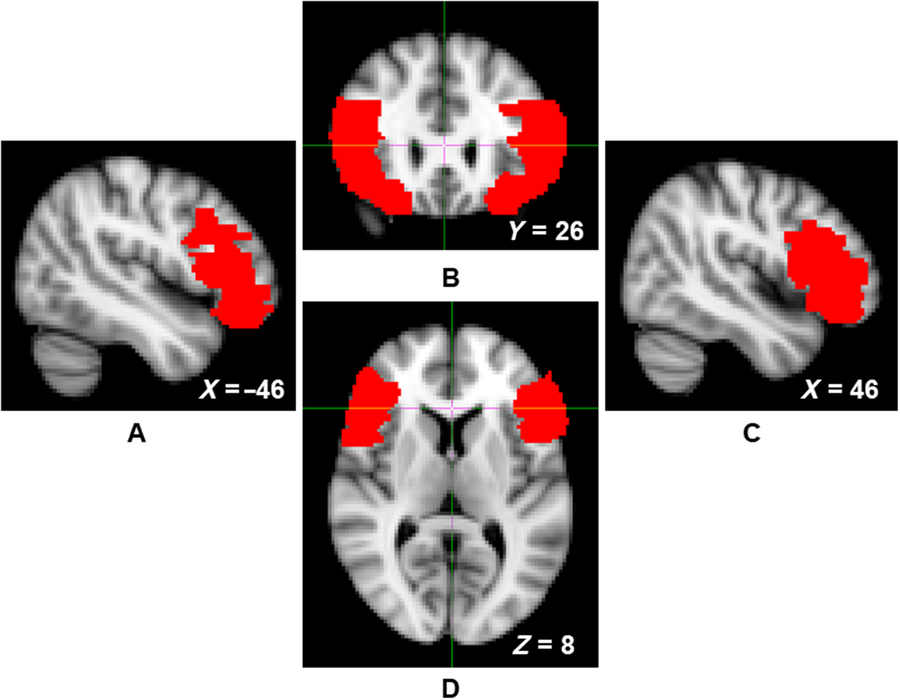

The Oxford Centre for Functional MRI of the Brain’s Software Library (FSL version 5.0) was used to conduct all pre-processing and voxel-based morphometry analyses (Smith et al., Reference Smith, Jenkinson, Woolrich, Beckmann, Behrens, Johansen-Berg and Matthews2004; Woolrich et al., Reference Woolrich, Jbabdi, Patenaude, Chappell, Makni, Behrens and Smith2009). Structural data were analyzed with FSL-VBM (Douaud et al., Reference Douaud, Smith, Jenkinson, Behrens, Johansen-Berg, Vickers and James2007; http://fsl.fmrib.ox.ac.uk/fsl/fslwiki/FSLVBM), an optimized VBM protocol (Good et al., Reference Good, Johnsrude, Ashburner, Henson, Friston and Frackowiak2001). First, structural images were brain-extracted and gray matter-segmented before being registered to the Montreal Neurological Institute (MNI 152) standard space using nonlinear registration (Andersson, Jenkinson, & Smith, Reference Andersson, Jenkinson and Smith2007). The resulting images were averaged and flipped along the x-axis to create a left-right symmetric, study-specific gray matter template. Second, all native gray matter images were nonlinearly registered to this study-specific template and modulated to correct for local expansion or contraction due to the nonlinear component of the spatial transformation. The modulated gray matter images were then smoothed with an isotropic Gaussian kernel (σ = 3.5 mm). Gray matter estimates were then extracted from this study-specific template to create density estimates for the left and right VLPFC of each participant. VLPFC masks were defined using the Automated Anatomical Labeling atlas mask for the opercular, triangular, and orbital aspects of the inferior frontal gyrus (Figure 1; Tzourio-Mazoyer et al., Reference Tzourio-Mazoyer, Landeau, Papathanassiou, Crivello, Etard, Delcroix and Joliot2002).

Figure 1. Left sagittal (panel A), coronal (panel B), right sagittal (panel C), and axial (panel D) views of the ventrolateral prefrontal cortex (VLPFC) mask, indicated by red voxels.